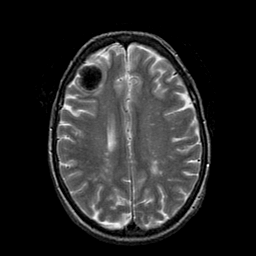

Metastatic Adenocarcinoma of the Colon: T2-weighted MR -- Slice #16

[Home][Help][Clinical] Slice 16